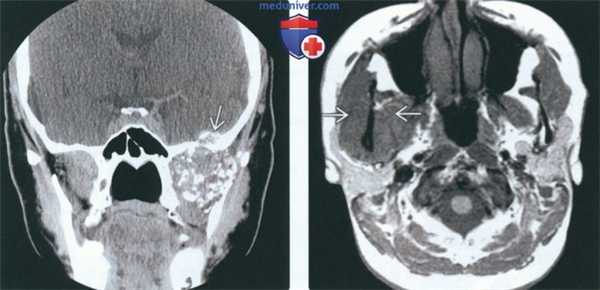

(Слева) КТ с КУ, мягкотканное окно. Другой пример хондросаркомы жевательного пространства, на этот раз без кальцификатов. Образование низкой плотности окружает ветвь нижней челюаи и распространяется вокруг венечного отростка и мыщелка.

(Справа) КТ в костном окне, аксиальная проекция. Мыщелок и шейка нижней челюсти деформированы и содержат кальцификаты. Отсутствие характерных кальцификатов в мягкотканной части опухоли делает постановку диагноза затруднительной.

(Слева) На аксиальной КТ с КУ в мягкотканном окне визуализируется гиподенсная опухоль (хондросаркома без включений кальция), окружающая ветвь нижней челюсти и распространяющаяся вокруг венечного отростка и мыщелка.

(Справа) На аксиальной КТ в костном окне определяется вздутие мыщелка и шейки нижней челюаи с наличием хондроидных кальцинатов. Отсутствие типичных для хондросаркомы кальцинатов в мягкотканном компоненте затрудняет диагностику.